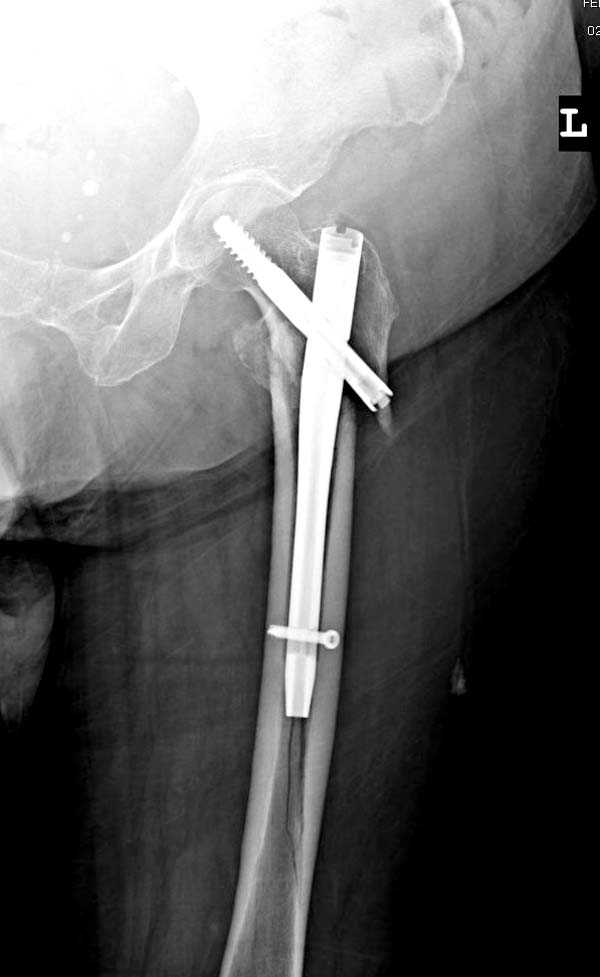

Здесь представлен случай, где в послеоперационном периоде обнаружена техническая ошибка, Gamma 3 установлен с нарушением методики. Больная в 91 лет, прооперирована через день после поступления и выписана через 48 часов.<br>

При первом послеоперационном поликлиническом осмотре больная предъявила жалобы на боли в бедре. В серийных снимках обнаружен продольный перелом верхнего отдела бедра.<br>

Считаем, что техническая ошибка произошла во время установки гвоздя, когда рассверливанию канала не уделили должного внимания. Канал остался узковат, и гвоздь был забит с силой.

Имя     : Gamma 3. 1.jpg